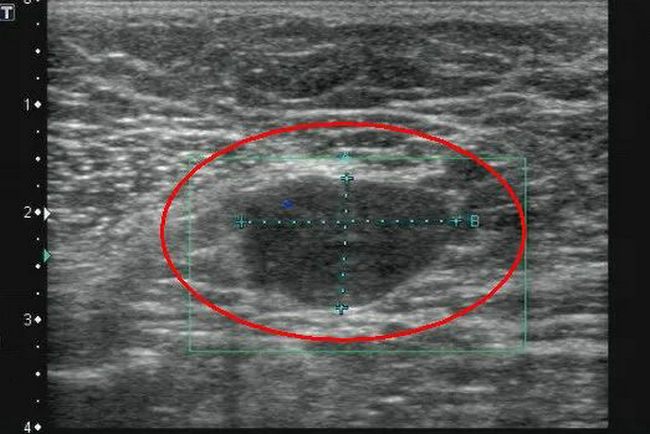

▲ 乳腺纤维腺瘤

超声报告单中,对于各类结节都会有详细描述,其中椭圆形或圆形、边界清晰、未见血流信号的以良性居多。而纵向生长、形态不规则、边缘不清楚、内有点状及簇状钙化、血流信号丰富的,则要警惕恶性病变的可能。